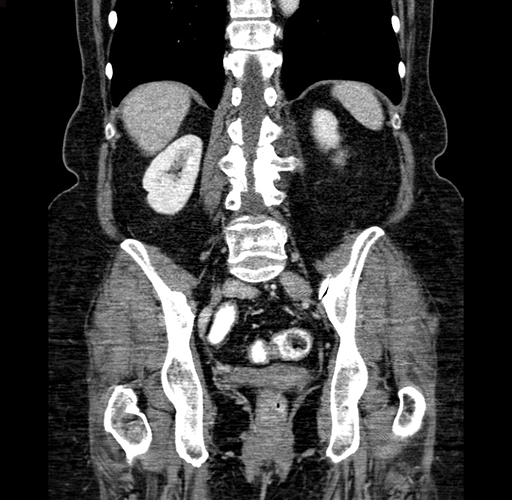

Pre-Chemo: Coronal Venous

Coronal Venous